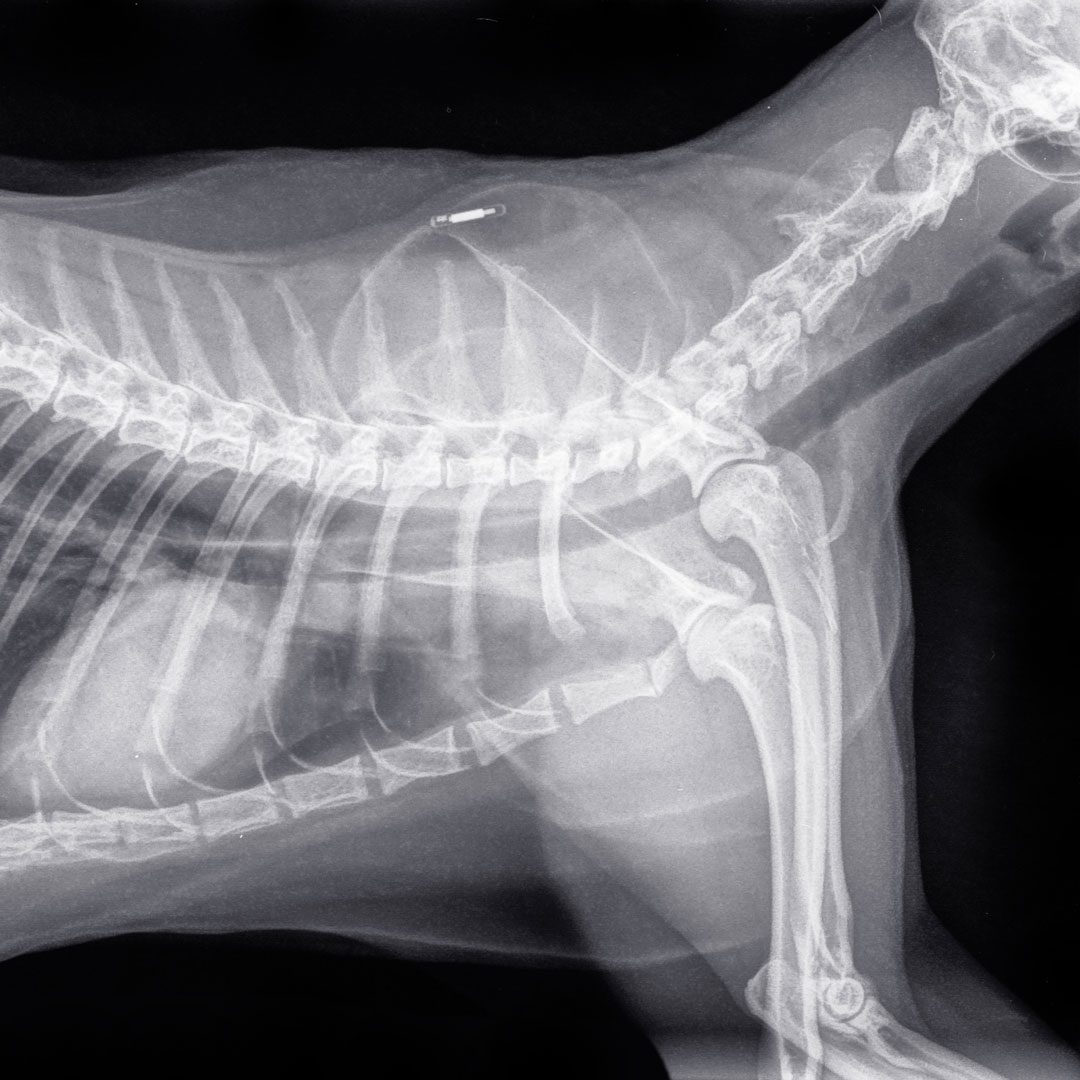

Digital X-Ray Imaging

Plainfield Veterinary Clinic & Surgical Center uses digital X-ray technology, which provides clear images almost instantly. Unlike traditional X-rays that require film development, digital imaging allows our veterinarians to view results right away and make quick diagnostic decisions.

Digital X-rays offer several advantages, including:

• Checkmark Icon

Faster image capture and results

Improved image clarity and detail

Less time needed for positioning

Reduced time under anesthesia for certain procedures

This technology is especially helpful for pets experiencing pain, injury, or trauma, as it allows our team to obtain diagnostic images quickly and efficiently.

Cat X Ray